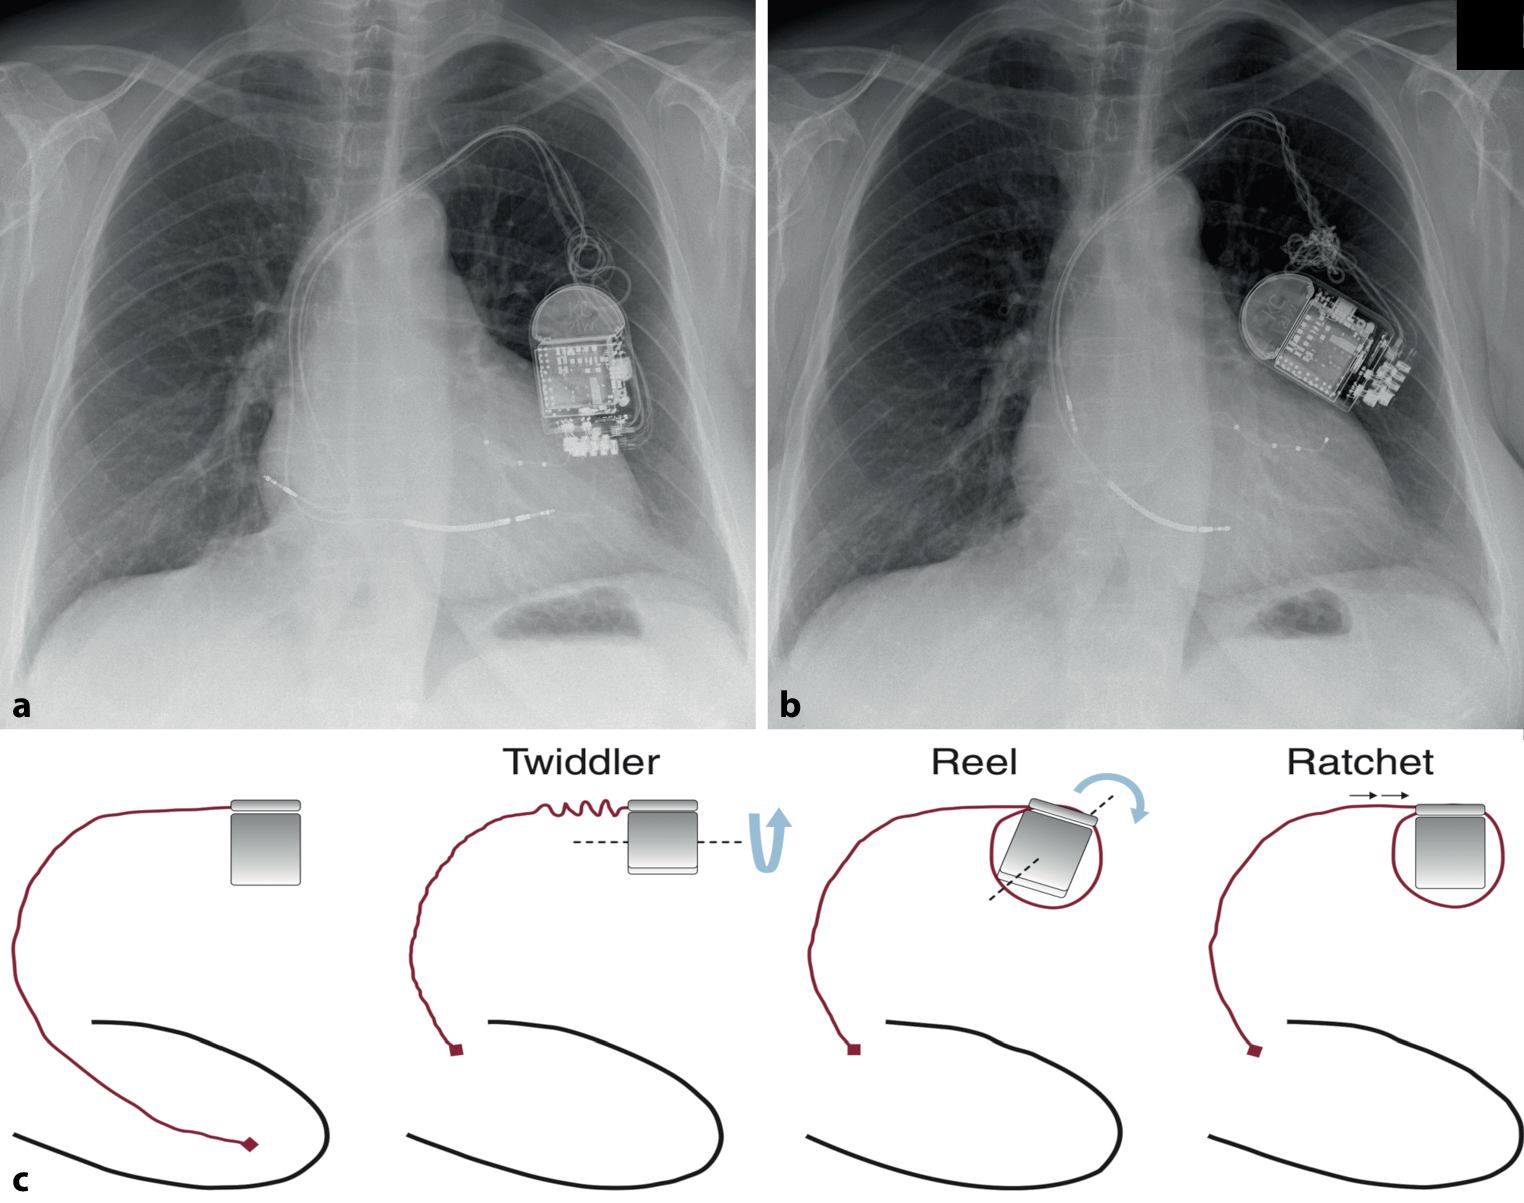

A 65-year-old woman with a cardiac resynchronisation therapy-defibrillator underwent routine device interrogation, revealing abnormalities in the atrial lead (reduced amplitude and occasional detection failure) and the right ventricular lead (increased pacing threshold) 13 months post-implantation. This prompted a chest X‑ray due to suspected lead dislodgement (Fig. 1b).

a Chest radiography taken four months earlier for an unrelated purpose, already showing a rotated generator with some lead twisting. However, it was not reviewed by a cardiologist at that time. b Chest radiography at presentation, revealing both Twiddler and Reel syndromes, with leftward rotation of the pulse generator, CRT‑D lead twisting, and dislodged atrial and right ventricular leads. The left ventricular lead remained properly positioned. The intense twisting and progression between (a) and (b) suggest compulsive generator manipulation by the patient. c Movements involving the generator or leads contributing to various macro-dislodgement syndromes. Reproduced with permission from Elsevier [1] ©. Not covered by this article’s CC BY 4.0 License. Reuse requires Elsevier’s permission

The X‑ray revealed twisted and macro-dislodged leads, along with pulse generator rotation, indicative of both Twiddler and Reel syndromes. These syndromes result from specific mechanisms of macro-dislodgement caused by movements of the generator or leads ([1]; Fig. 1c).